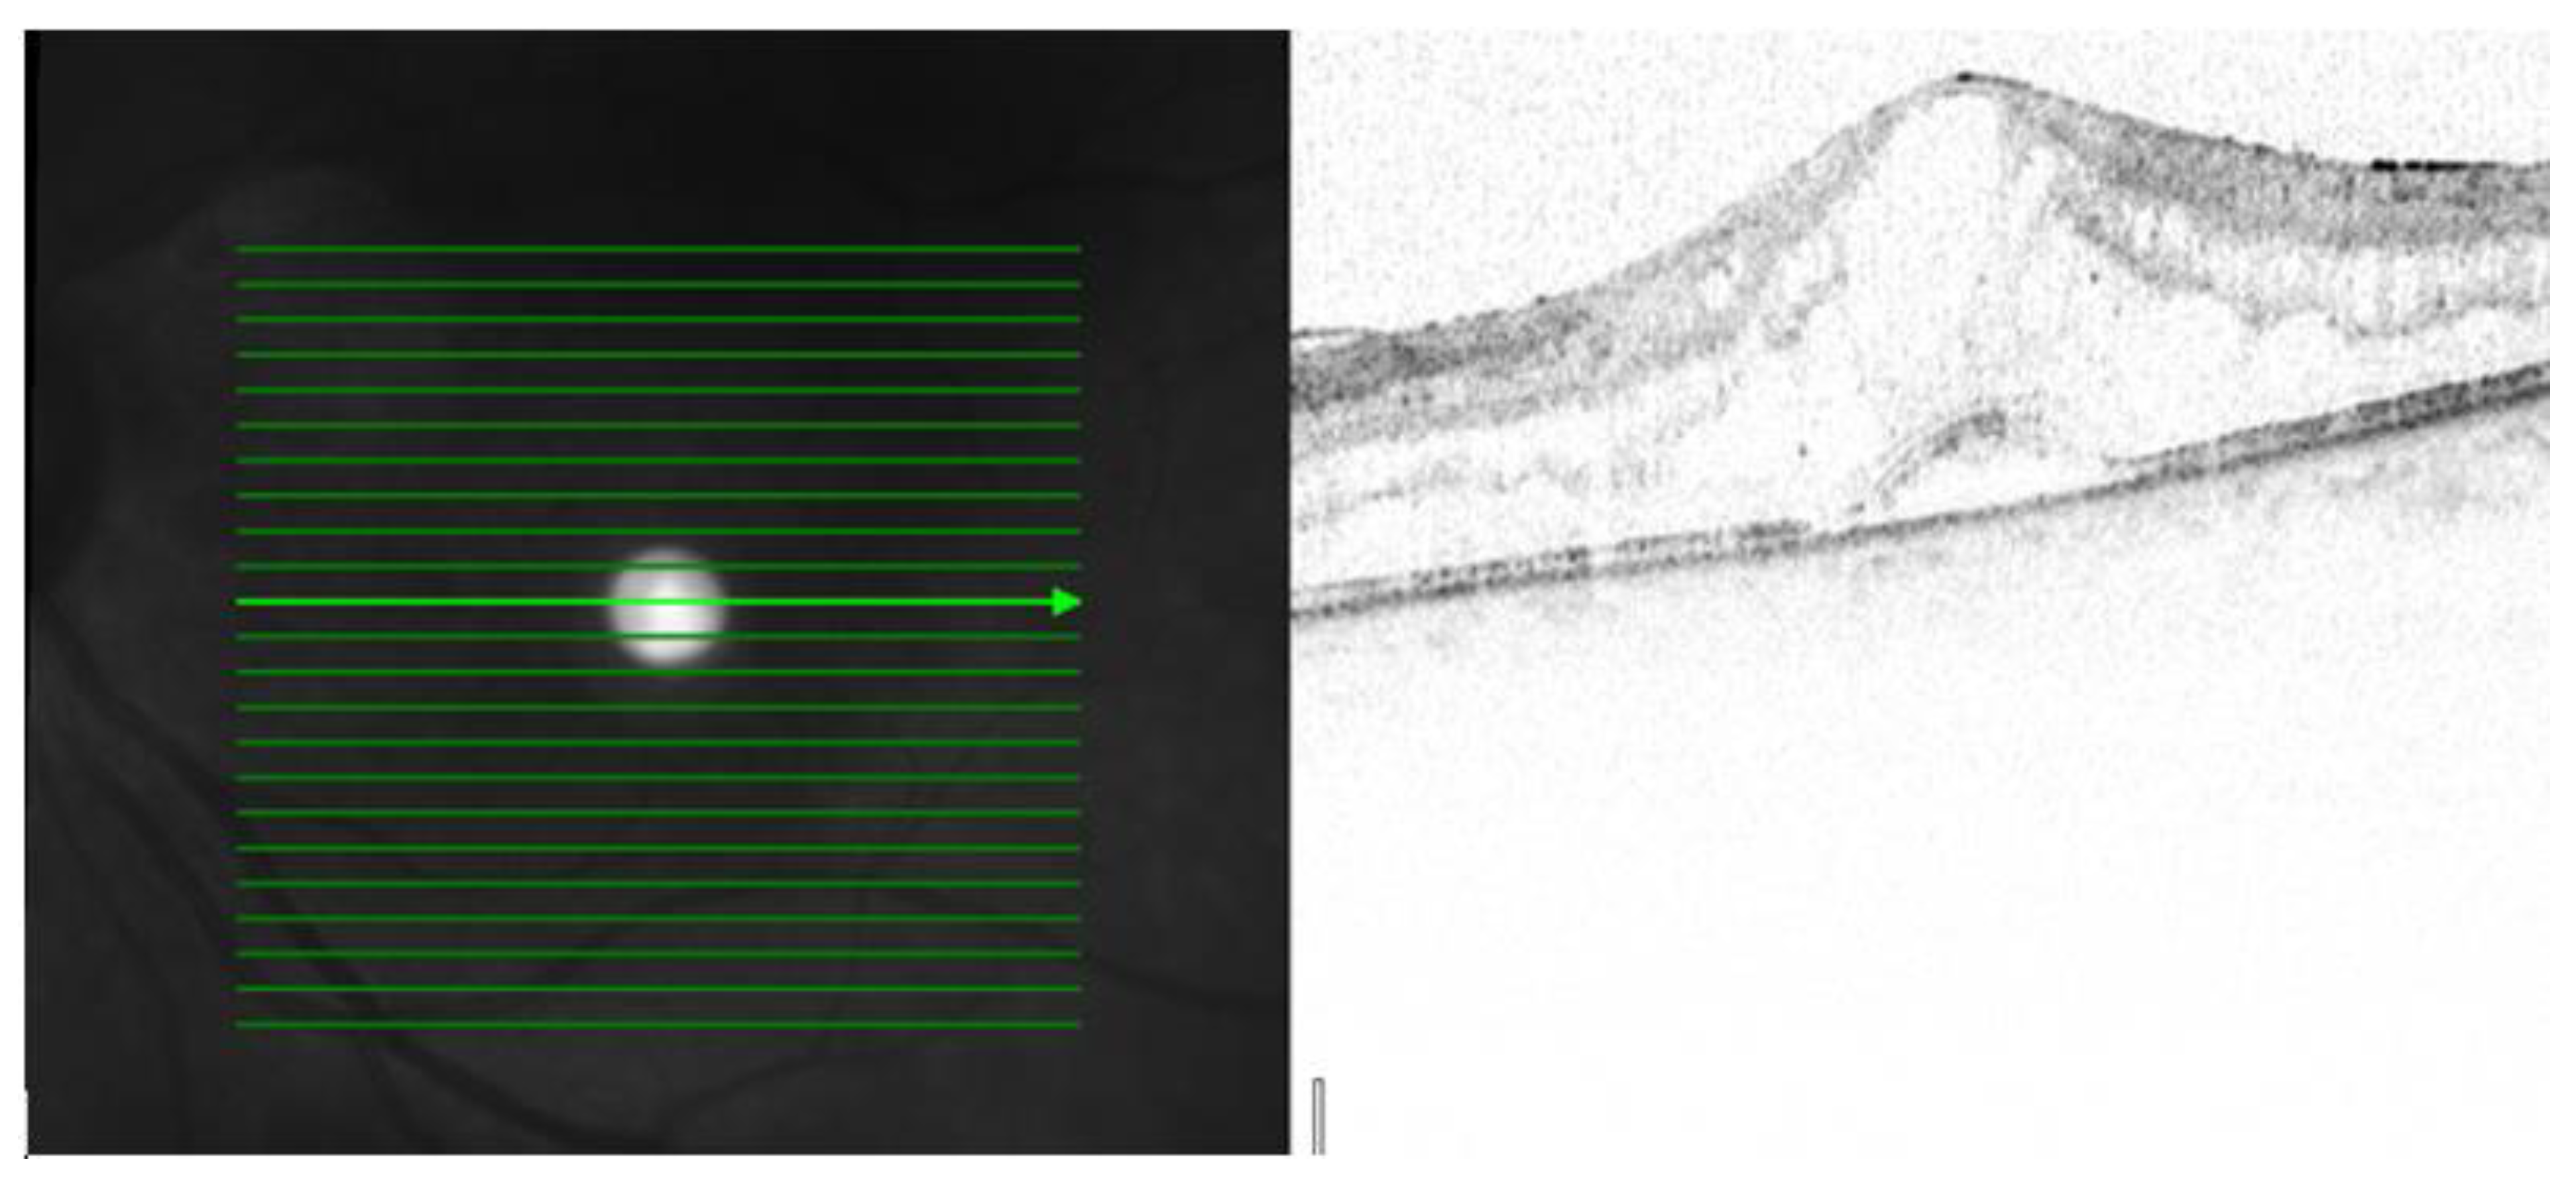

Figure 4. OCT image from left eye: In SRD, fluid accumulates in the subretinal space between the sensory retina and the retinal pigment epithelium. OCT scale: 512 × 496, high-speed mode, 20°.

Three patterns of macular edema can be revealed: Cystoid macular edema (CME) is the formation of fluid-filled cyst-like spaces between the outer plexiform and inner nuclear layer of the retina. Diffuse macular edema (DME) is characterized by the disturbance of the layered retinal structure or low reflective areas looking similar to a sponge. In serous retinal detachment (SRD), fluid accumulates in the subretinal space between the sensory retina and the retinal pigment epithelium [32] (Figure 2, Figure 3 and Figure 4).

Serous detachments, with the elevation of the retina, occur in a variety of disorders, including central serous chorioretinopathy (CSC), age-related macular degeneration (AMD), systemic lupus erythematosus (SLE), and choroidal ischemic disorders, such as accelerated hypertension, pre-eclampsia, eclampsia, systemic corticosteroid usage, or in some choroidal tumors and inflammatory disorders, for example, in Vogt–Koyanagi–Harada’s disease [18].